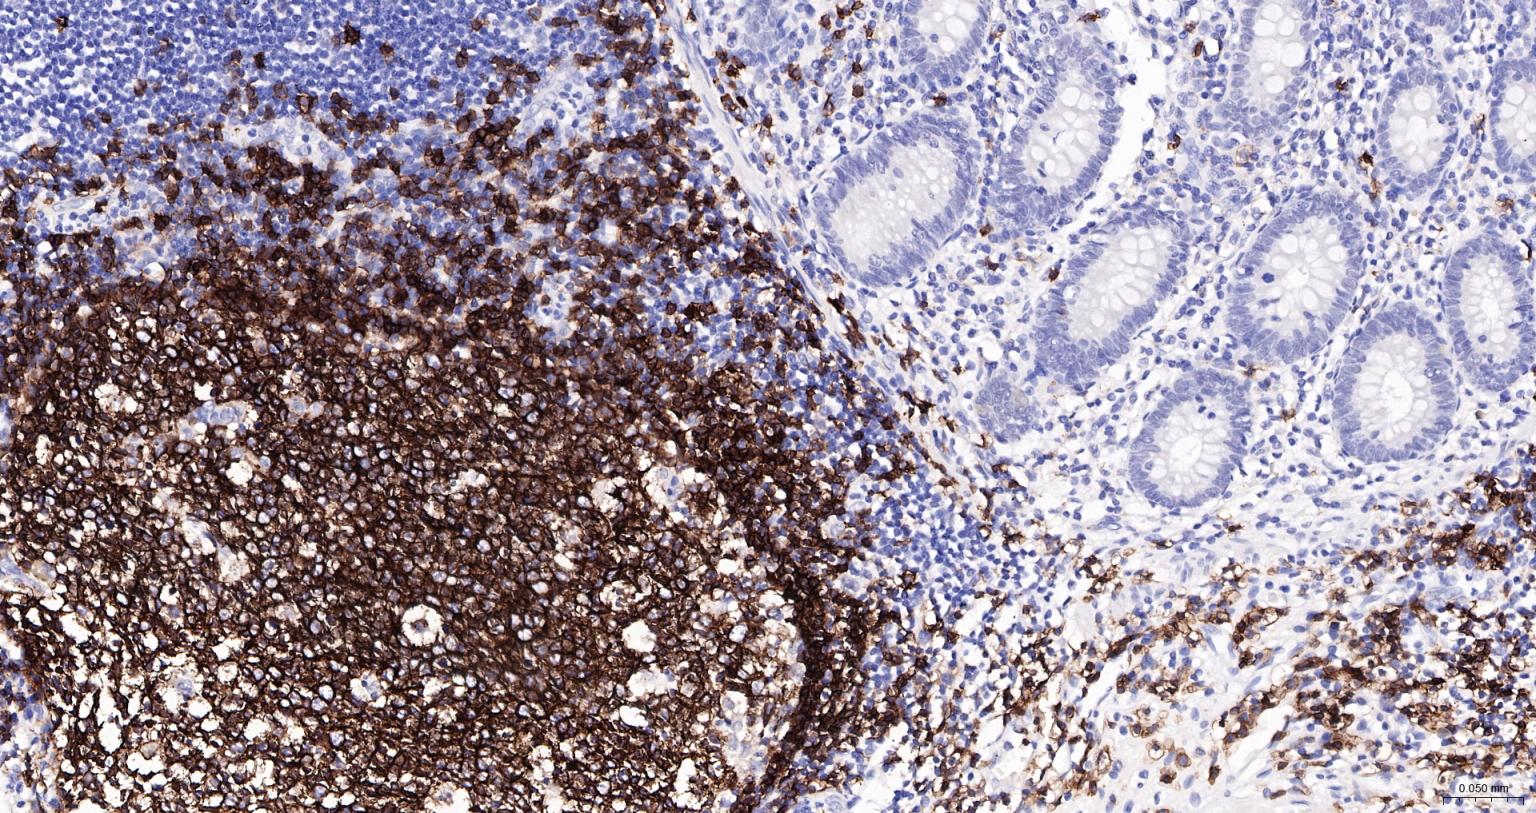

Paraformaldehyde-fixed, paraffin embedded Human appendix; Antigen retrieval by boiling in sodium citrate buffer (pH6.0) for 15 min; The section was incubated with CD20 Recombinant Monoclonal Antibody (bsm-60638R-HRP) at 1:200 overnight at 4°C, and DAB (C-0010) staining.